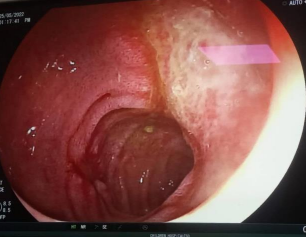

An 8 year old boy presented to the emergency department of Children Hospital Faisalabad with abdominal pain and black stools for last 4-5 days. He had blunt trauma to the back when during playing his siblings jumped over his back repeatedly after which he developed melena. He was initially managed by a paediatric surgeon who after baseline workup and consultation with radiologist did CT abdomen with contrast and found clots of blood in stomach and bilateral gluteal hematomas (Fig.1) he put drains in anterolateral aspects of his both thighs.

Figure 1, 2, 3

Figure 1